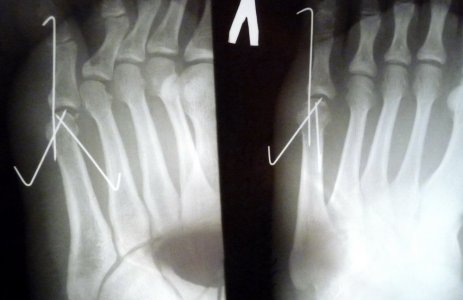

Мне 22 года. Перепрыгивая через забор, неудачно приземлился. В травмпункте сказали, что это перелом головки пятой плюсневой кости со смещением. Просверлили кость в мизинце и поставили натяжение. Через 5 дней снимок показал, что обломок на место не встал. Меня прооперировали и поставили три спицы.

Через 5 недель сделали снимок

и спицы сняли. Сказали, что еще 2 недели не наступать на ногу. После этого прошла неделя. Опухоль до конца не спала.

3. На левом рентгене стопы под углом 45 грудусов виден маленький осколок. Он безвреден или его все же стоит удалить хирургически?